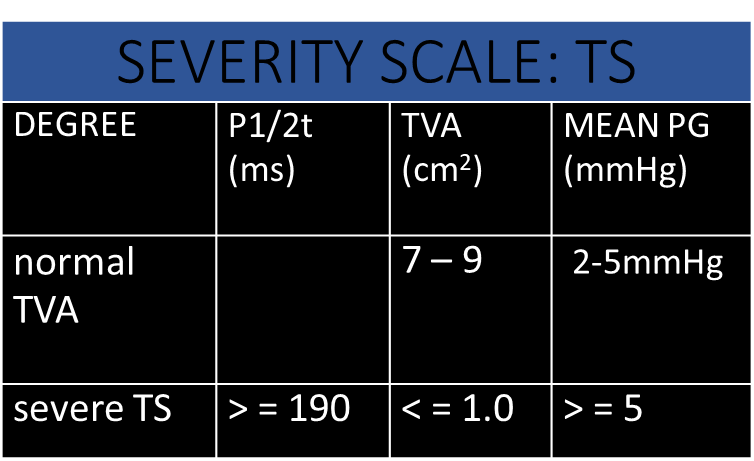

Severity Scale